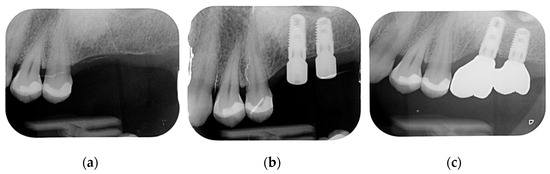

The final diagnosis of idiopathic osteosclerosis was confirmed. A six-month follow-up showed good healing, and prosthesis on dental implants was performed (Figure 8, Figure 9 and Figure 10).

Figure 9.

Juxta-gingival view of the surgical site: (a) preoperative view; (b) implants’ placement; (c) prosthetic on implants.